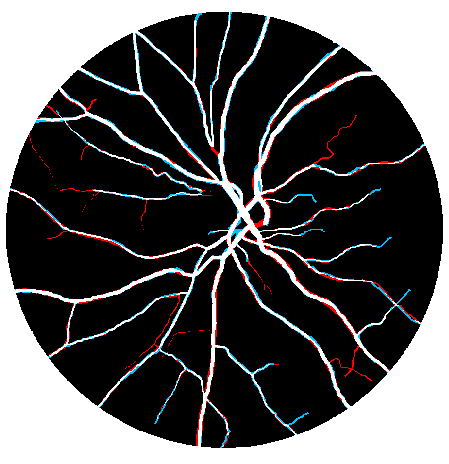

4.1 Validation of the Base System

We started by evaluating our Base System regarding data augmentation, prediction and regularization. The results of each variant are shown in Table 3, while the probabilistic predictions can be seen in Fig. 4. All tests were performed under the same conditions, with the only source of variability being the component under study.

Considering the Base System as the reference, we can see that reducing the number of patches by four strongly deteriorated the results in terms of Acc and AUC. Besides this, either when using original or elastic patches to keep the initial number of samples, the differences to the reference remained almost the same. Looking directly at Fig. 4, we notice that these approaches favored the simultaneous appearance of FN and FP, with elastic patches leading to greater tortuosity in the detected vessel segments. Overall, this hints that the network benefited the most from the information encoded by the rotations. Another important note is related to the way those rotations were presented to the network. Recalling section 2.4, we have seen that some data augmentation strategies designed for FC-CNNs (Dieleman et al.,, 2016; Worrall et al.,, 2016) require the rotated versions to be arranged consecutively. The Consecutive Rotations test hints that a deterministic proximity between the rotated patches is detrimental to the performance of the FCN, with the network showing more difficulties in detecting vessel segments as can be seen in Fig. 4.

When facing the randomly placed rotations used in the Base System, all the alternatives were found to be prejudicial with statistical significance.